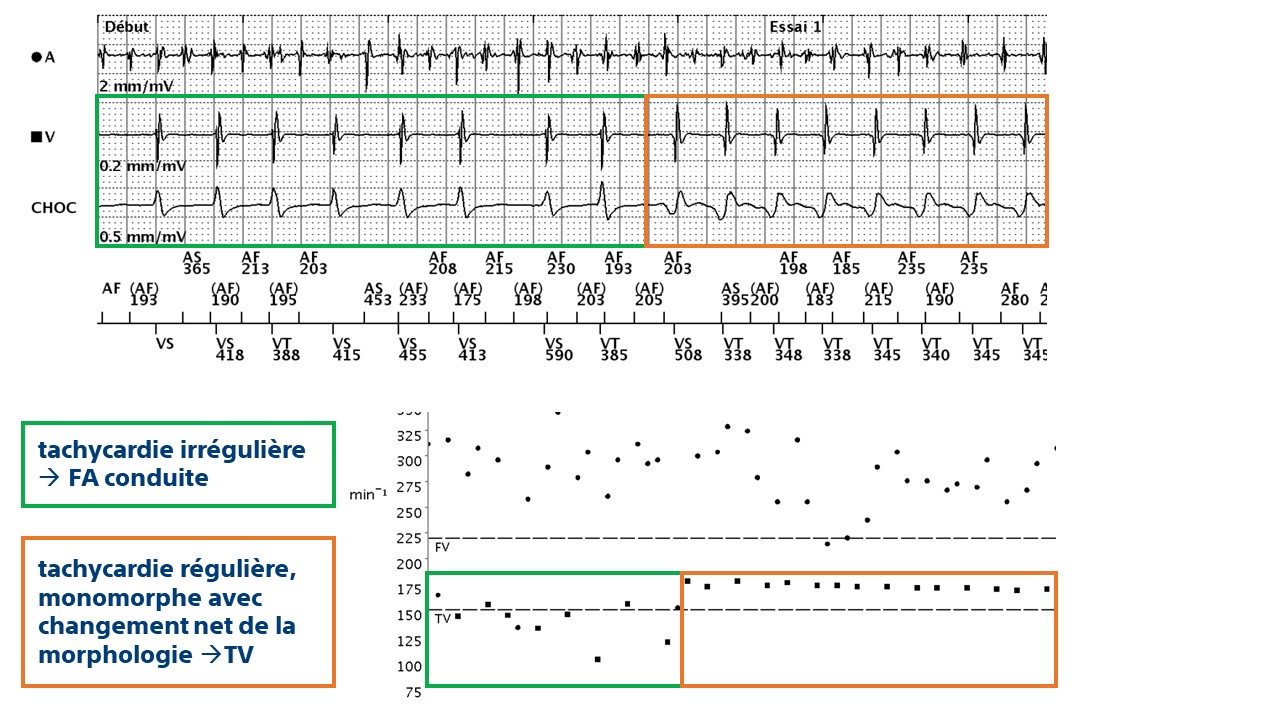

Ce tracé montre un aspect caractéristique de double tachycardie (FA + TV) : l'activité atriale est rapide et polymorphe (cycles correctement classés FA) ; le canal ventriculaire montre une accélération brutale avec une tachycardie régulière, monomorphe avec changement net de la morphologie du signal sur le canal de choc (TV) ; le dispositif diagnostique la double tachycardie (V>A : Faux, RID-, FA, rythme stable) et délivre les thérapies

- ce tracé montre l'intérêt de coupler les discriminateurs pour le diagnostic de tachycardies complexes comme les bitachycardies ; la discrimination est opérée par étapes

- dans cet exemple, le dispositif retrouve un diagnostic de FA avec un rythme stable (diagnostic de bitachycardie) et les thérapies sont délivrées